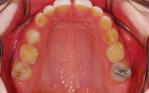

Orthodontic closure of the front gap and replacement of the loose baby teeth with some permanent implant crowns and bridgework.

Before